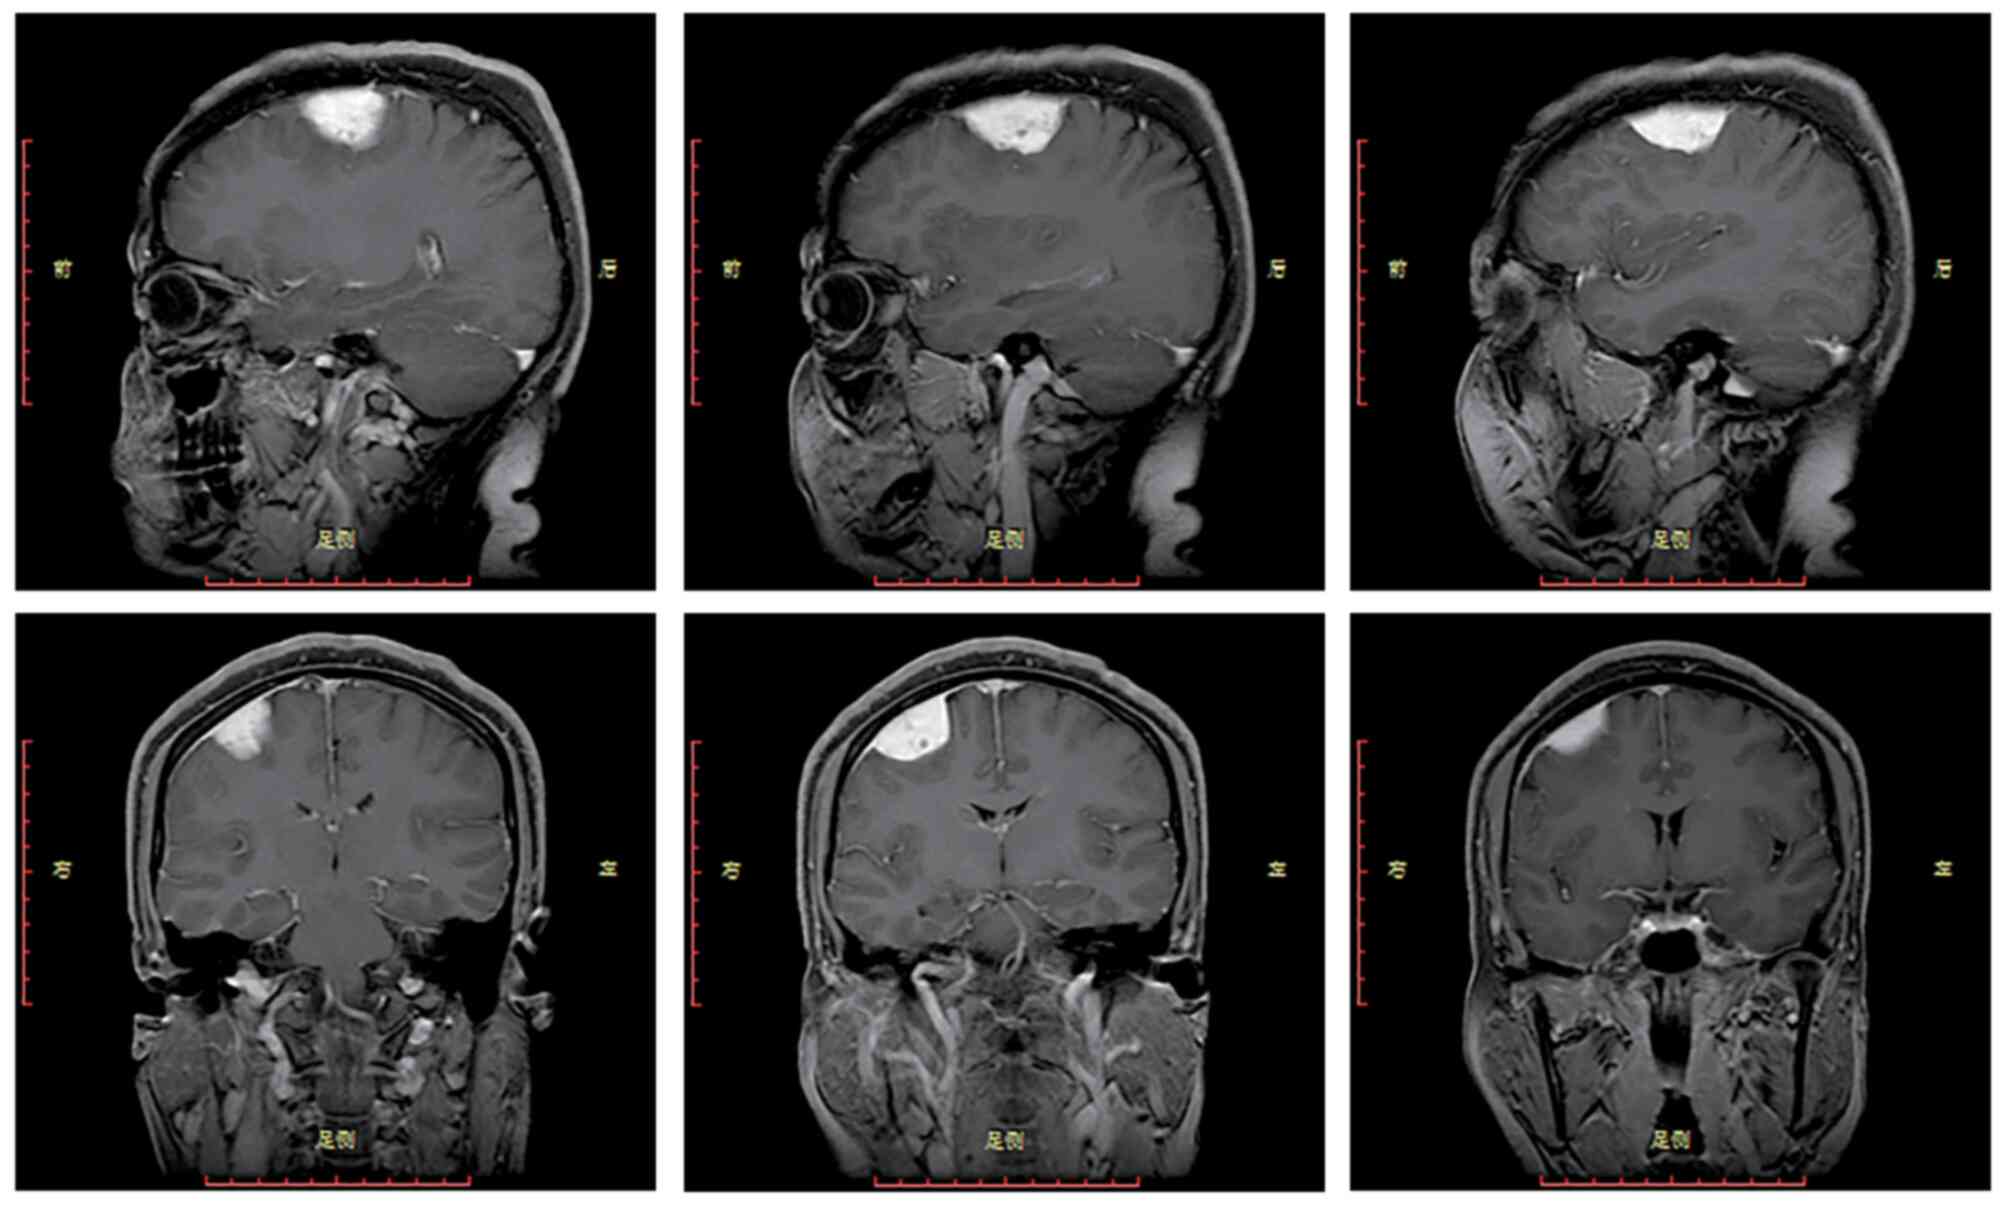

Angiomatous meningioma with bizarre nuclei: A case report

Angiomatous meningioma (AM) is a relatively rare subtype of WHO grade I meningioma. A relatively rare case of AM was recently encountered in a 45‑year‑old woman. The present case not only observed the typical AM histological pattern but also a large number of cells with bizarre, large, deeply staining and unevenly distributed nuclei. These cells with bizarre nuclei showed a similar pattern of immunoreactivity as meningeal epithelial cells. Although the presence of a large number of cells with bizarre nuclei in this case increased tumour cell atypia, the cells did not differ with regard to proliferative activity and mitotic imaging. Therefore, the patient was ultimately diagnosed as having AM with bizarre nuclei, WHO grade I. This manifestation of nuclear atypia and pleomorphism may be due to ‘degenerative changes’ in pre‑existing, long‑established vascular lesions, similar to those seen in degenerative schwannomas and symplastic haemangioma, rather than being considered an indicator of malignancy.

Figure 1